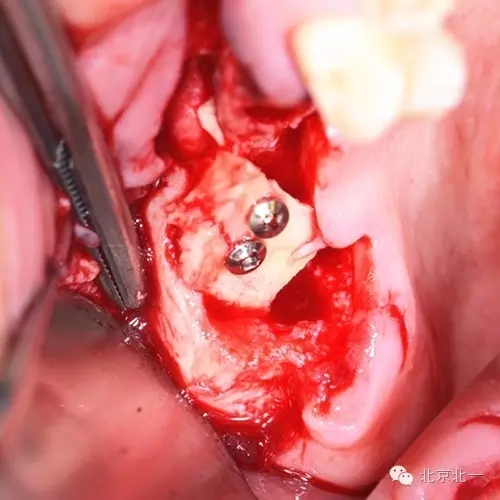

圖五:手術(shù)區(qū)可見拔牙窩

圖六:修整骨塊

圖七:骨塊堅強內(nèi)固定